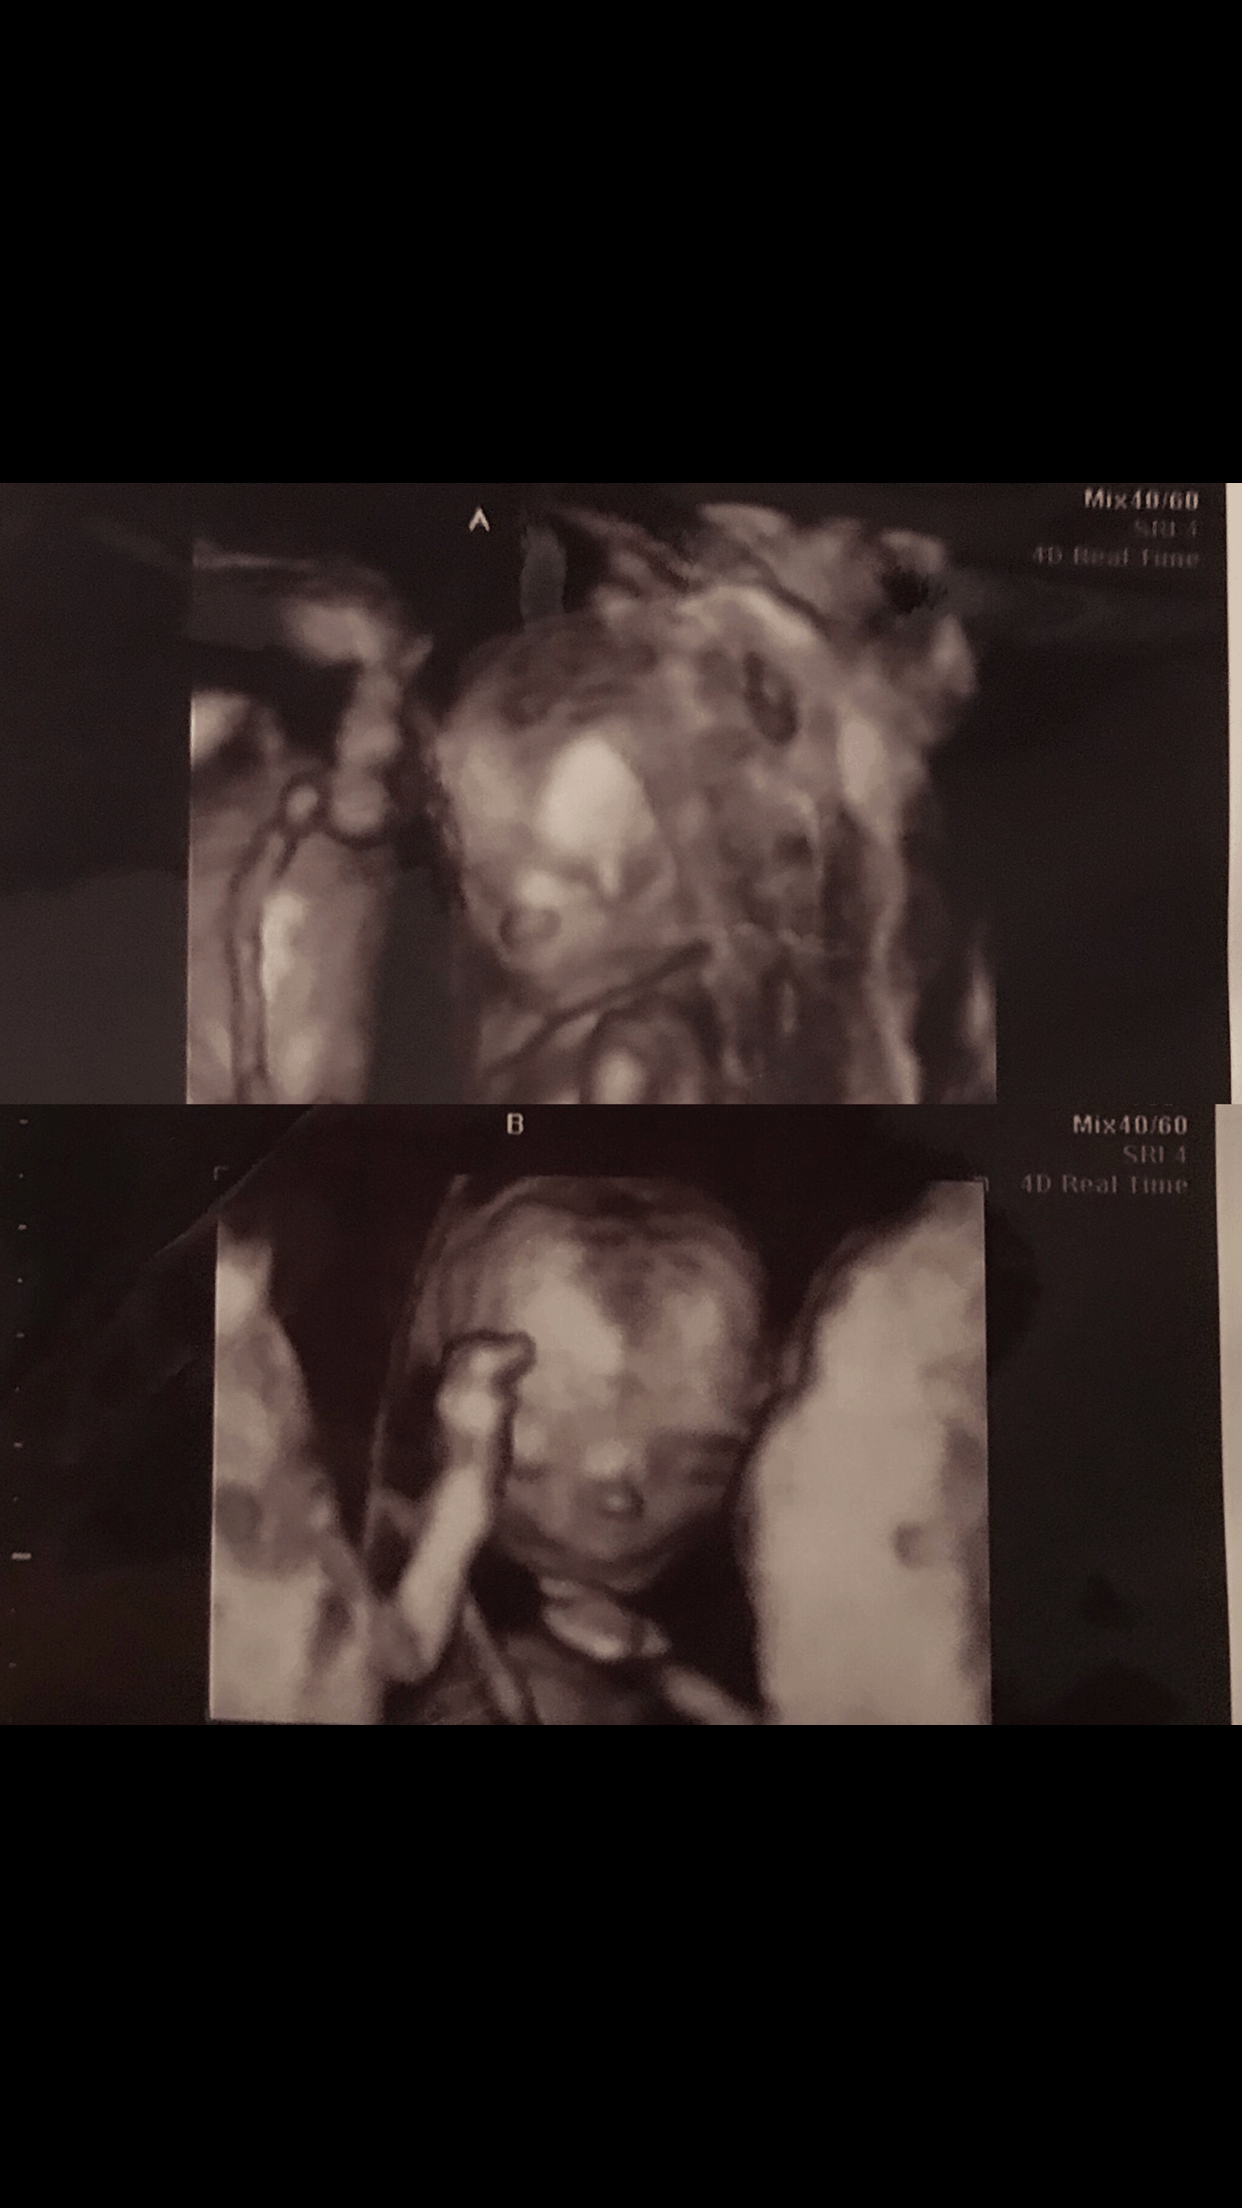

Ultrasound Photos at 15 Weeks Pregnant With Twins